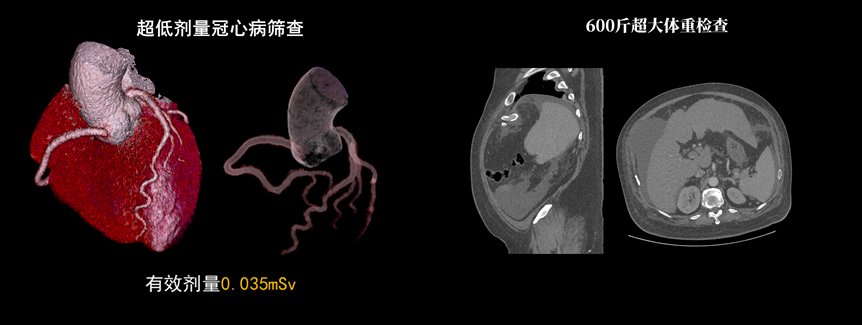

液態(tài)金屬軸承球管,陽(yáng)極直冷技術(shù),提供30MHU球管熱容量,可高通量連續(xù)掃描。AI劑量調(diào)制、迭代重建等復(fù)合劑量控制方案,為體檢患者提供優(yōu)化劑量掃查。82cm大孔徑,讓大體型患者檢查更加舒適。

天河640CT的寬體探測(cè)器單圈掃描即可覆蓋全心臟,搭配快速機(jī)架轉(zhuǎn)速和獨(dú)家AI冠脈追焦技術(shù),可實(shí)現(xiàn)單心動(dòng)周期內(nèi)無(wú)限心率、無(wú)限心律的冠脈成像,對(duì)于嚴(yán)重心律不齊、房顫、房撲,超高心率等情況,天河640CT都能在單心動(dòng)周期內(nèi)獲得優(yōu)質(zhì)圖像。